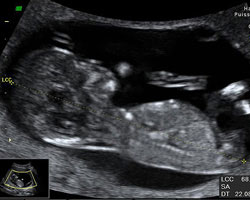

Ecografia de 13 semanas

Na 13ª semana de gravidez o bebé mede entre seis e oito centímetros do cocuruto até às nádegas e pesa aproximadamente 23 gramas.

Idade do feto: 11 semanas.